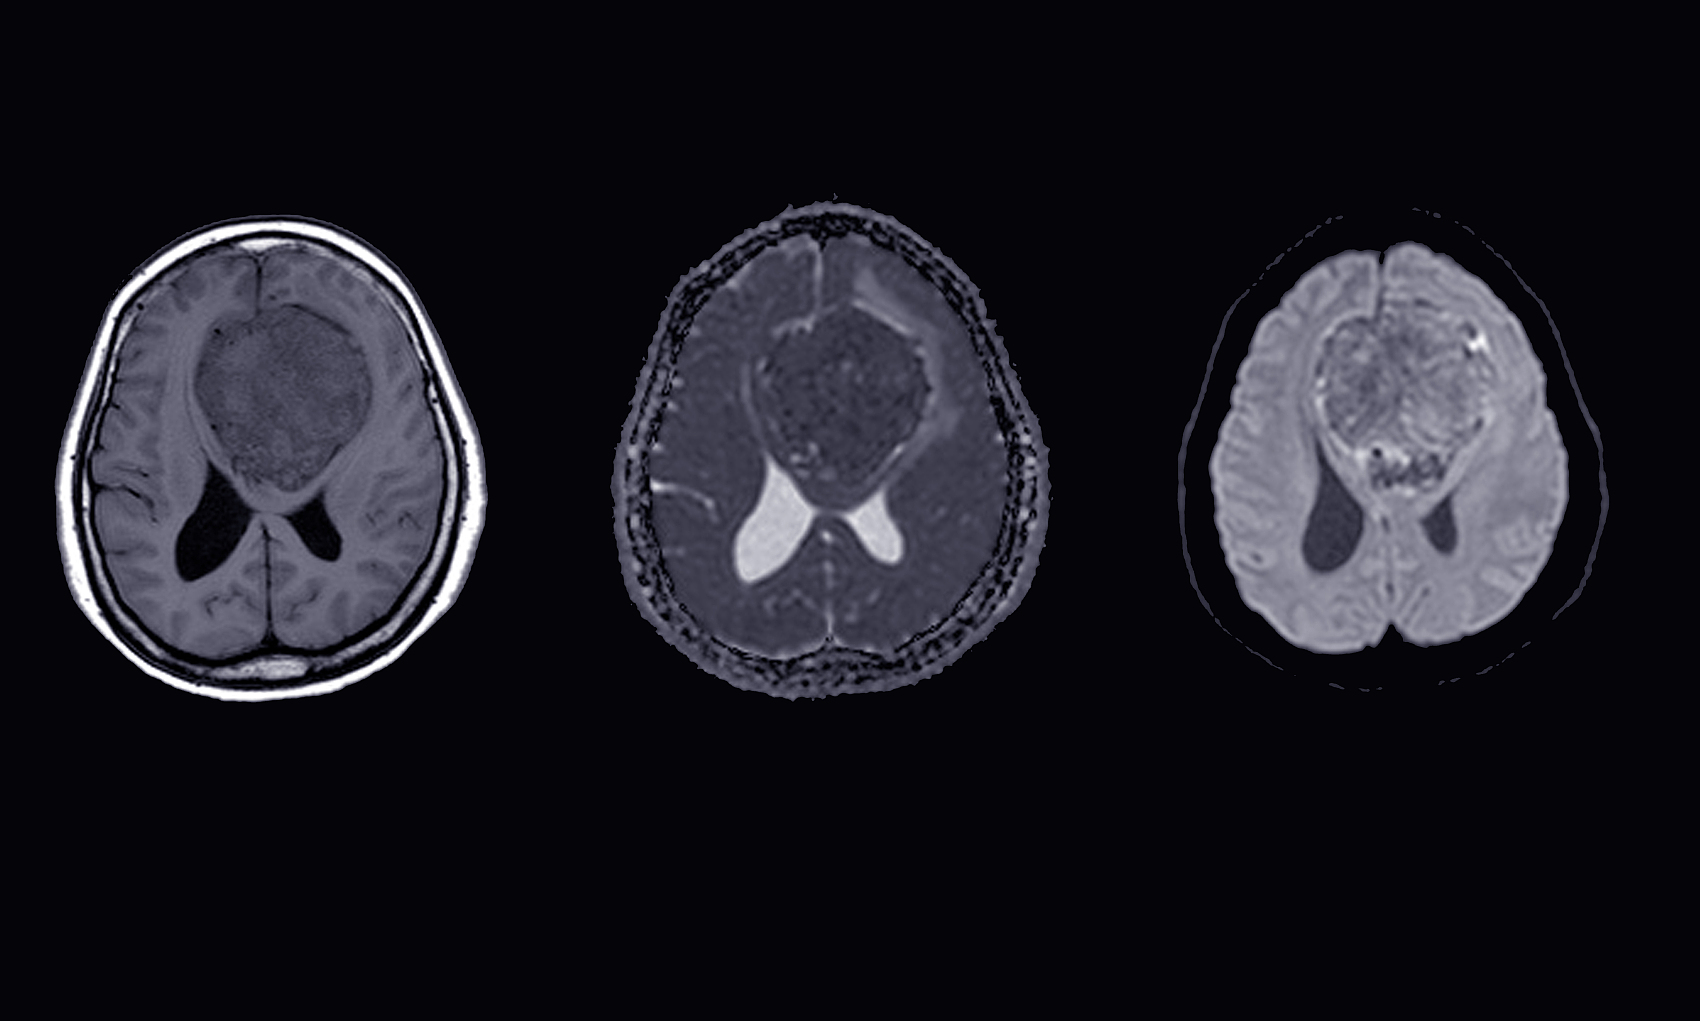

脑膜瘤放射治疗医院,昆明脑膜瘤医院哪家好-昆明医科肿瘤医院脑膜瘤是一种生长在脑膜上的肿瘤,它可能是恶性的也可能是良性的。对于一些较大或难以手术的脑膜瘤,放射治疗可能是一种有效的治疗方法。本文将介绍脑膜瘤放射治疗的原理、过程、风险和预后。脑膜瘤放射治疗的原理脑膜...

脑膜瘤放疗效果怎么样,昆明脑膜瘤医院哪家好-昆明医科肿瘤医院脑膜瘤是一种起源于脑膜的肿瘤,它的治疗方法包括手术切除、放射治疗、化学治疗或这些治疗的组合。在治疗中,放射治疗通常是主要的治疗方法之一。那么,脑膜瘤放疗的效果如何呢?下面我们就来详细探讨。放疗是一种以...

脑膜瘤的早期症状,昆明脑膜瘤医院推荐-昆明医科肿瘤医院脑膜瘤(Meningiomas)是起源于脑膜及脑膜间隙的衍生物,发病率占颅内肿瘤的19.2%,居第2位,女性:男性为2:1,发病高峰年龄在45岁,儿童少见。许多无症状脑膜瘤多为偶然发现。脑膜瘤是一种起源于脑...

脑膜瘤的临床表现,昆明脑膜瘤医院哪家好-昆明医科肿瘤医院脑膜瘤是一种常见的颅内肿瘤,它通常发生在脑膜(覆盖脑部和脊髓的薄膜)上。由于它的位置和生长速度不同,其症状和表现也会因个体差异而有所不同。但是,一些常见的症状和诊断方法可以帮助医生和患者及时发现和治疗脑膜...

昆明脑膜瘤放射治疗方式,昆明脑膜瘤医院哪家好-昆明医科肿瘤医院脑膜瘤(Meningiomas)是起源于脑膜及脑膜间隙的衍生物,发病率占颅内肿瘤的19.2%,居第2位,女性:男性为2:1,发病高峰年龄在45岁,儿童少见。许多无症状脑膜瘤多为偶然发现。脑膜瘤是指发...

脑膜瘤放射治疗医院,昆明脑膜瘤医院哪家好-昆明医科肿瘤医院脑膜瘤是一种发生在脑膜(脑部外层覆盖的薄膜)上的肿瘤。它通常是良性的,但在某些情况下也可能是恶性的。脑膜瘤的治疗通常需要一个综合治疗方案,其中包括手术切除、放射治疗和化疗。放射治疗是一种常用的治疗方法,...

脑膜瘤放射治疗技术,昆明脑膜瘤医院哪家好-昆明医科肿瘤医院脑膜瘤是一种起源于脑膜的肿瘤,它可能会对患者的生命和健康造成重大威胁。对于一些脑膜瘤患者,放射治疗可能是一种有效的治疗方法。在本文中,我们将讨论放射治疗如何对脑膜瘤进行治疗,以及患者需要了解的相关信息。...

脑膜瘤放射治疗效果,昆明脑膜瘤医院哪家好-昆明医科肿瘤医院脑膜瘤是一种比较常见的颅内肿瘤,通常生长缓慢,但如果不及时治疗,可能会对患者的生命和健康造成严重威胁。目前,放射治疗被广泛应用于脑膜瘤的治疗中,已经成为治疗脑膜瘤的重要手段之一。放射治疗通过高能量的放射...